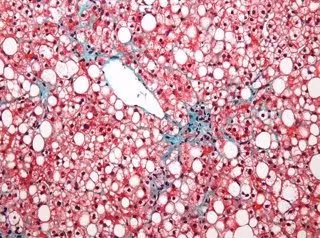

Descubren nuevos determinados implicados en el desarrollo de la enfermedad del hígado grado no alcohólico

Hígado graso

SINC/WIKIPEDIA